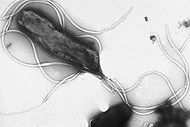

H. pylori is a helix-shaped (classified as a curved rod, not spirochaete) Gram-negative bacterium about 3 micrometres long with a diameter of about 0.5 micrometres. It is microaerophilic; that is, it requires oxygen, but at lower concentration than is found in the atmosphere. It contains a hydrogenase which can be used to obtain energy by oxidizing molecular hydrogen (H2) produced by intestinal bacteria. It produces oxidase, catalase, and urease. It is capable of forming biofilms and can convert from spiral to a possibly viable but nonculturable coccoid form, both likely to favour its survival and be factors in the epidemiology of the bacterium.

H. pylori possesses five major outer membrane protein (OMP) families. The largest family includes known and putative adhesins. The other four families are porins, iron transporters, flagellum-associated proteins, and proteins of unknown function. Like other typical Gram-negative bacteria, the outer membrane of H. pylori consists of phospholipids and lipopolysaccharide (LPS). The O antigen of LPS may be fucosylated and mimic Lewis blood group antigens found on the gastric epithelium. The outer membrane also contains cholesterol glucosides, which are found in few other bacteria. H. pylori has four to six lophotrichous flagella; all gastric and enterohepatic Helicobacter species are highly motile owing to flagella. The characteristic sheathed flagellar filaments of Helicobacter are composed of two copolymerized flagellins, FlaA and FlaB.

To colonize the stomach, H. pylori must survive the acidic pH of the lumen and use its flagella to burrow into the mucus to reach its niche, close to the stomach's epithelial cell layer. Many bacteria can be found deep in the mucus, which is continuously secreted by mucus-secreting cells and removed on the luminal side. To avoid being carried into the lumen, H. pylori senses the pH gradient within the mucus layer by chemotaxis and swims away from the acidic contents of the lumen towards the more neutral pH environment of the epithelial cell surface. H. pylori is also found on the inner surface of the stomach epithelial cells and occasionally inside epithelial cells. It produces adhesins which bind to membrane-associated lipids and carbohydrates and help it adhere to epithelial cells. For example, the adhesin BabA binds to the Lewis b antigen displayed on the surface of stomach epithelial cells. H. pylori produces large amounts of the enzyme urease, molecules of which are localized inside and outside of the bacterium. Urease breaks down urea (which is normally secreted into the stomach) to carbon dioxide and ammonia. The ammonia is converted to ammonium by accepting a proton (H+), which neutralizes gastric acid. The survival of H. pylori in the acidic stomach is dependent on urease. The ammonia produced is toxic to the epithelial cells, and, along with the other products of H. pylori—including proteases, vacuolating cytotoxin A (VacA), and certain phospholipases,— damages those cells.